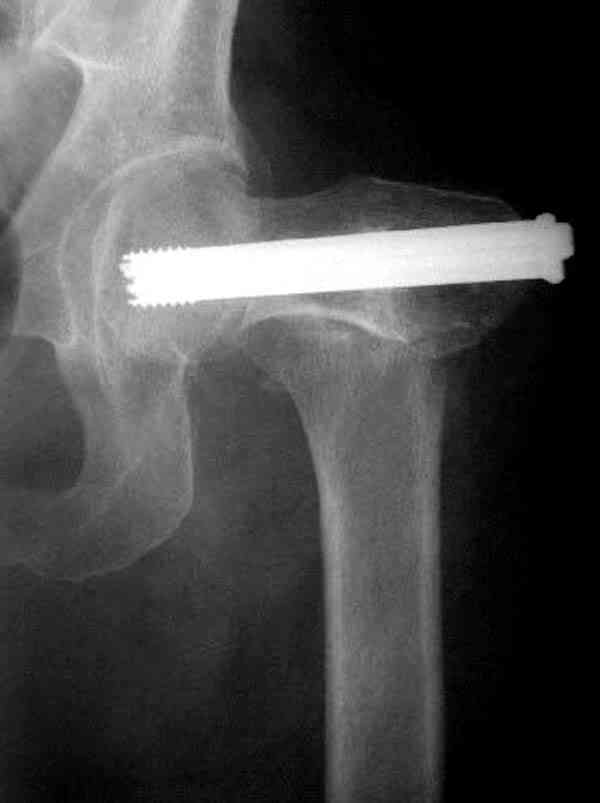

Здесь случай перелома из-за ослабления латерального кортекса через 3 недели после операции на шейке. Шурупы были установлены под большим углом, слабый латеральный кортекс не выдержал нагрузку.

Коллега Челноков прав, здесь еще имеется риск перелома за счет ослабления латерального кортекса. Во время установки канюлированных шурупов за редким исключением спица вводится с одного раза, множественные попытки ослабляют латеральный кортекс, что станет источником перелома в этом месте.

В идеале для профилактики рефрактуры шурупы надо вводить не больше, чем под 130 градусным углом и не ниже уровня малого вертела.

Насчет биомеханических преимуществ одного шурупа  тоже возникает вопрос. Если придерживаться канонов механики, для перелома шейки необходимо 3 паралельных шурупа, расположенных ближе к кортикальному слою шейки.